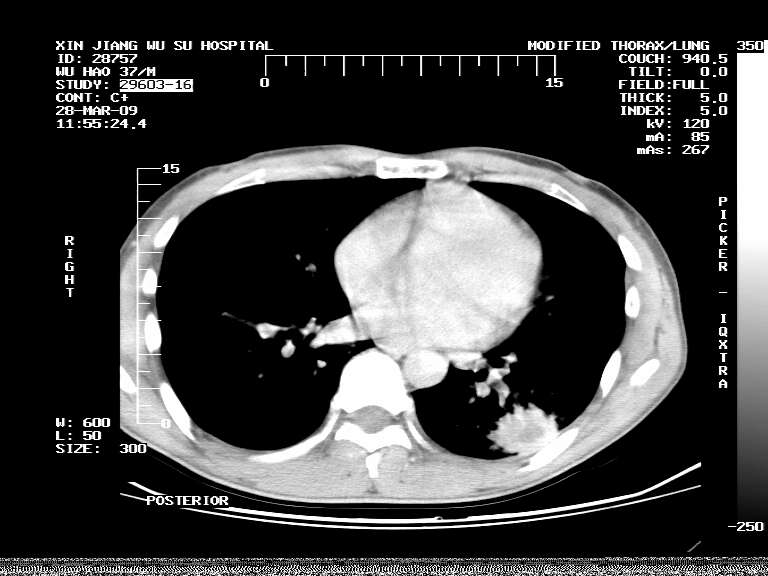

男,37岁,体检胸透发现阴影。

患者体检发现 无症状 左肺下叶占位,边缘模糊,可见血管聚束、分叶、胸膜牵拉,增强呈不均匀性强化。 首先考虑左肺下叶周围型肺癌,建议穿刺活检。

患者体检发现 无症状 左肺下叶占位,边缘模糊,可见血管聚束、分叶、胸膜牵拉,增强呈不均匀性强化。 首先考虑左肺下叶周围型肺癌,建议穿刺活检。支持!

左肺下叶见一结节病变,边缘欠清不光滑,与胸膜粘连且胸膜局限性增厚,注药后呈环形强化,动脉期壁呈明显点环状强化,静脉期壁强化减低,中心密度低无强化,灶周无明显的卫星灶和水肿区(晕征)---考虑周围性肺癌,不除外感染性病变,建议穿刺活检。

左肺下叶软组织病灶,密度较高,内见点状钙化,其周围见子灶,邻近胸膜扁平样增厚.c+病灶强化明显,中心强化弱.诊断:左肺下叶结核瘤.

周围有卫星灶,胸膜反应不明显,病灶中心有坏死。建议先抗结核治疗后,短期复查

左肺下叶大片实变影,内靠胸膜见不规则更高密度结节灶,边缘强化,相邻胸膜增厚,胸膜下脂肪线存在。考虑炎症,结核可能。